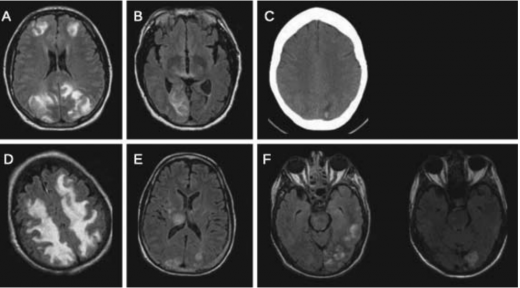

התמונה ההדמייתית האופיינית ב- CT או Magnetic Resoance Imaging) MRI) היא של בצקת מוקדית סימטרית. האונות האוקסיפיטליות (Occipital) והפריטאליות (Parietal) הן המעורבות בשכיחות הגבוהה ביותר ואחריהן האונה הפרונטאלית (Frontal), החלק התחתון של החיבור בין האונה הטמפוראלית (Temporal) והאוקסיפיטאלית ולבסוף הצרבלום (Cerebellum).

הממצא האופייני ב-MRI הוא היפראינטנסיות (Hyperintensity) ברצף T2 הנגרמת כנראה בשל בצקת ואזוגנית תת-קליפתית של החומר הלבן. ממצאים פתולוגיים בולטים אף יותר ברצף FLAIR (Fluid Attenuated Inversion Recovery) אשר מאפשר להבחין בשינויים עדינים.

בנוסף, שימוש ברצפי Diffusion-Weighted Imaging) DWI) ו-Apparent Diffusion Coefficient) ADC), עוזר להבדיל בין בצקת ואזוגנית, שהיא המרכיב המשמעותי ב-PRES, לבין בצקת ציטוטוקסית (Cytotoxic) שמאפיינת נזק מוקדי איסכמי (תמונה 1).

בבצקת ואזוגנית שהיא המרכיב העיקרי ב-PRES, האזורים ההיפראינטנסיים ב-T2 מתאימים ב-DWI לאזורים היפראינטנסיים או איזואינטנסיים (Isointense). ב-ADC אזורים אלה יראו גם הם בהירים יותר, בניגוד לנזק איסכמי (המבטא בצקת ציטוטוקסית) בה יראו אזורים אלה ב-ADC כהים.

רזולוציה (Resolution) מלאה של ממצאי ההדמיה נחשבת כמעט כהגדרה של התסמונת על אף שלא ברור התזמון המיטבי לביצוע הדמיית ביקורת (תמונה 2), אך היא מתרחשת כנראה בין פרק זמן של ימים בודדים עד שבועות [11], [2]. על אף התמונה המתוארת כאופיינית, קיימים מקרים רבים בהם ההדמיה אינה תואמת את תיאור זה. תוארו מקרים עם מעורבות קדמית משמעותית. יש גם מקרים מתועדים של מעורבות קורטיקאלית (Cortical), נזקים בלתי הפיכים נקודתיים, דימומים לתוך נגעים ומעורבות חד צדדית (תמונה 3).